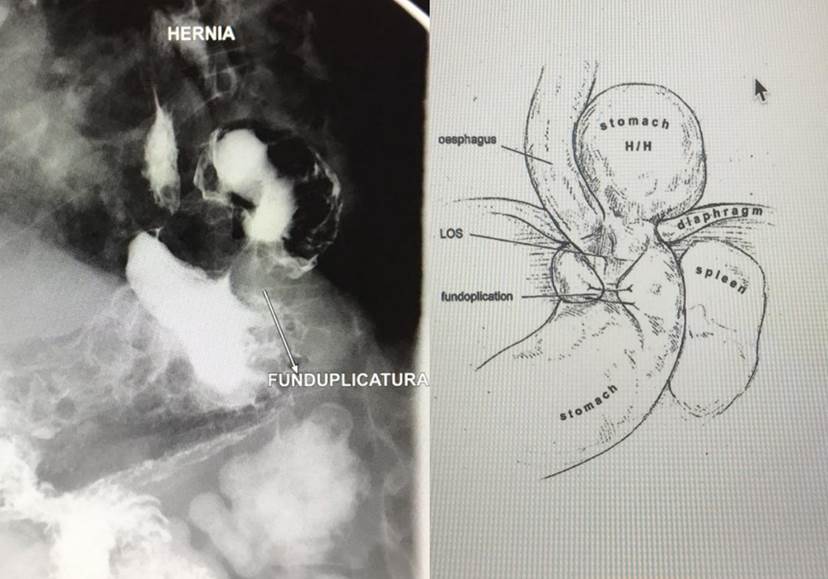

Un tránsito contrastado digestivo superior permite en este caso identificar el tipo de recidiva herniaria, con migración parcial del fundus gástrico hacia el tórax paraesofágico izquierdo, y una funduplicatura continente pero realizada técnicamente en por debajo de lo deseable (cuerpo alto) (figura 1).

Fig.1 Ilustración tomada de: Suppiah A. et als. Temporal patterns of hiatus hernia recurrence and hiatal failure: quality of life and recurrence after revision surgery. Dis Esophagus. 2017 Apr 1;30(4):1-8.